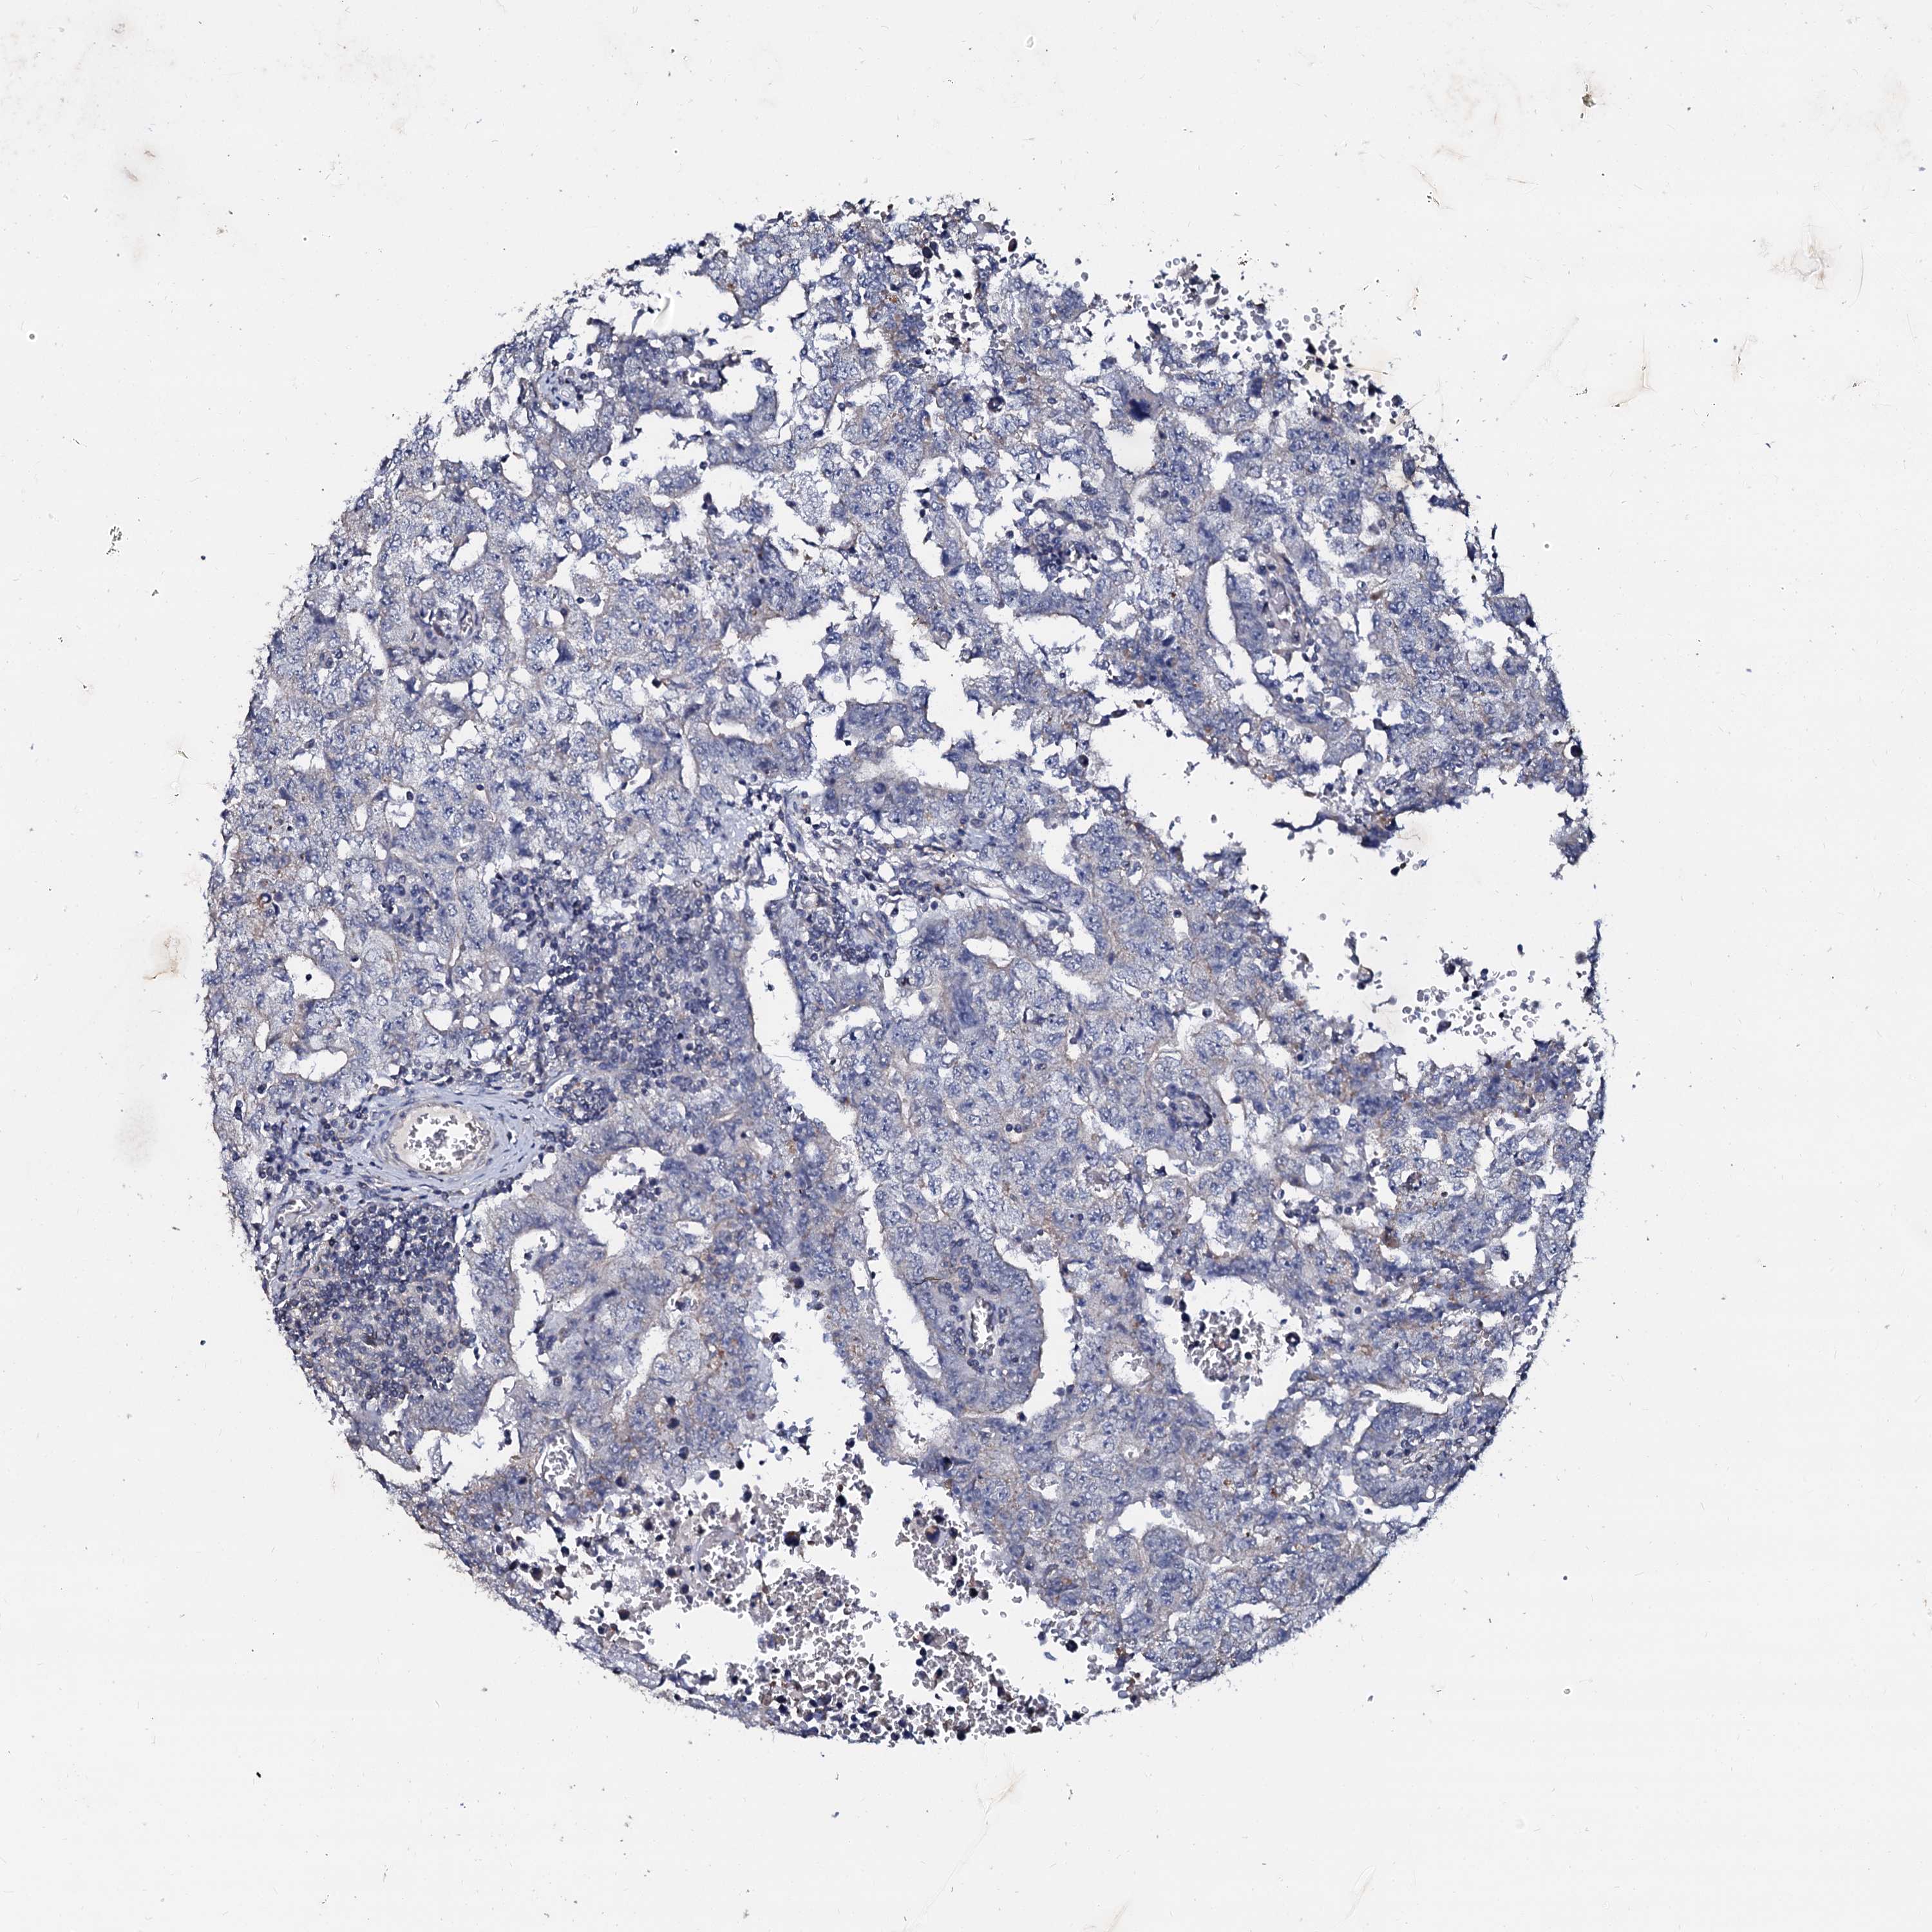

TESTIS CANCER - Protein expressioni

A mouse-over function shows sample information and annotation data. Click on an image to view it in a full screen mode. Samples can be filtered based on level of antibody staining by selecting one or several of the following categories: high, medium, low and not detected. The assay and annotation is described here.

Note that samples used for immunohistochemistry by the Human Protein Atlas do not correspond to samples in the TCGA dataset.

Antibody stainingi

Antibody staining in the annotated cell types in the current human tissue is reported as not detected, low, medium, or high, based on conventional immunohistochemistry profiling in selected tissues. This score is based on the combination of the staining intensity and fraction of stained cells.

Each image is clickable and will lead to virtual microscopy that enables deeper exploration of all samples and also displays staining intensity scores, fraction scores and subcellular localization as well as patient and tissue information for each sample.

Antibody HPA038939

Antibody HPA038940

Staining

High

Medium

Low

Not detected

Intensity

Strong

Moderate

Weak

Negative

Quantity

>75%

75%-25%

<25%

None

Location

Nuclear

Cytoplasmic/membranous

Cytoplasmic/membranous,nuclear

Carcinoma, Embryonal, NOS

Seminoma, NOS